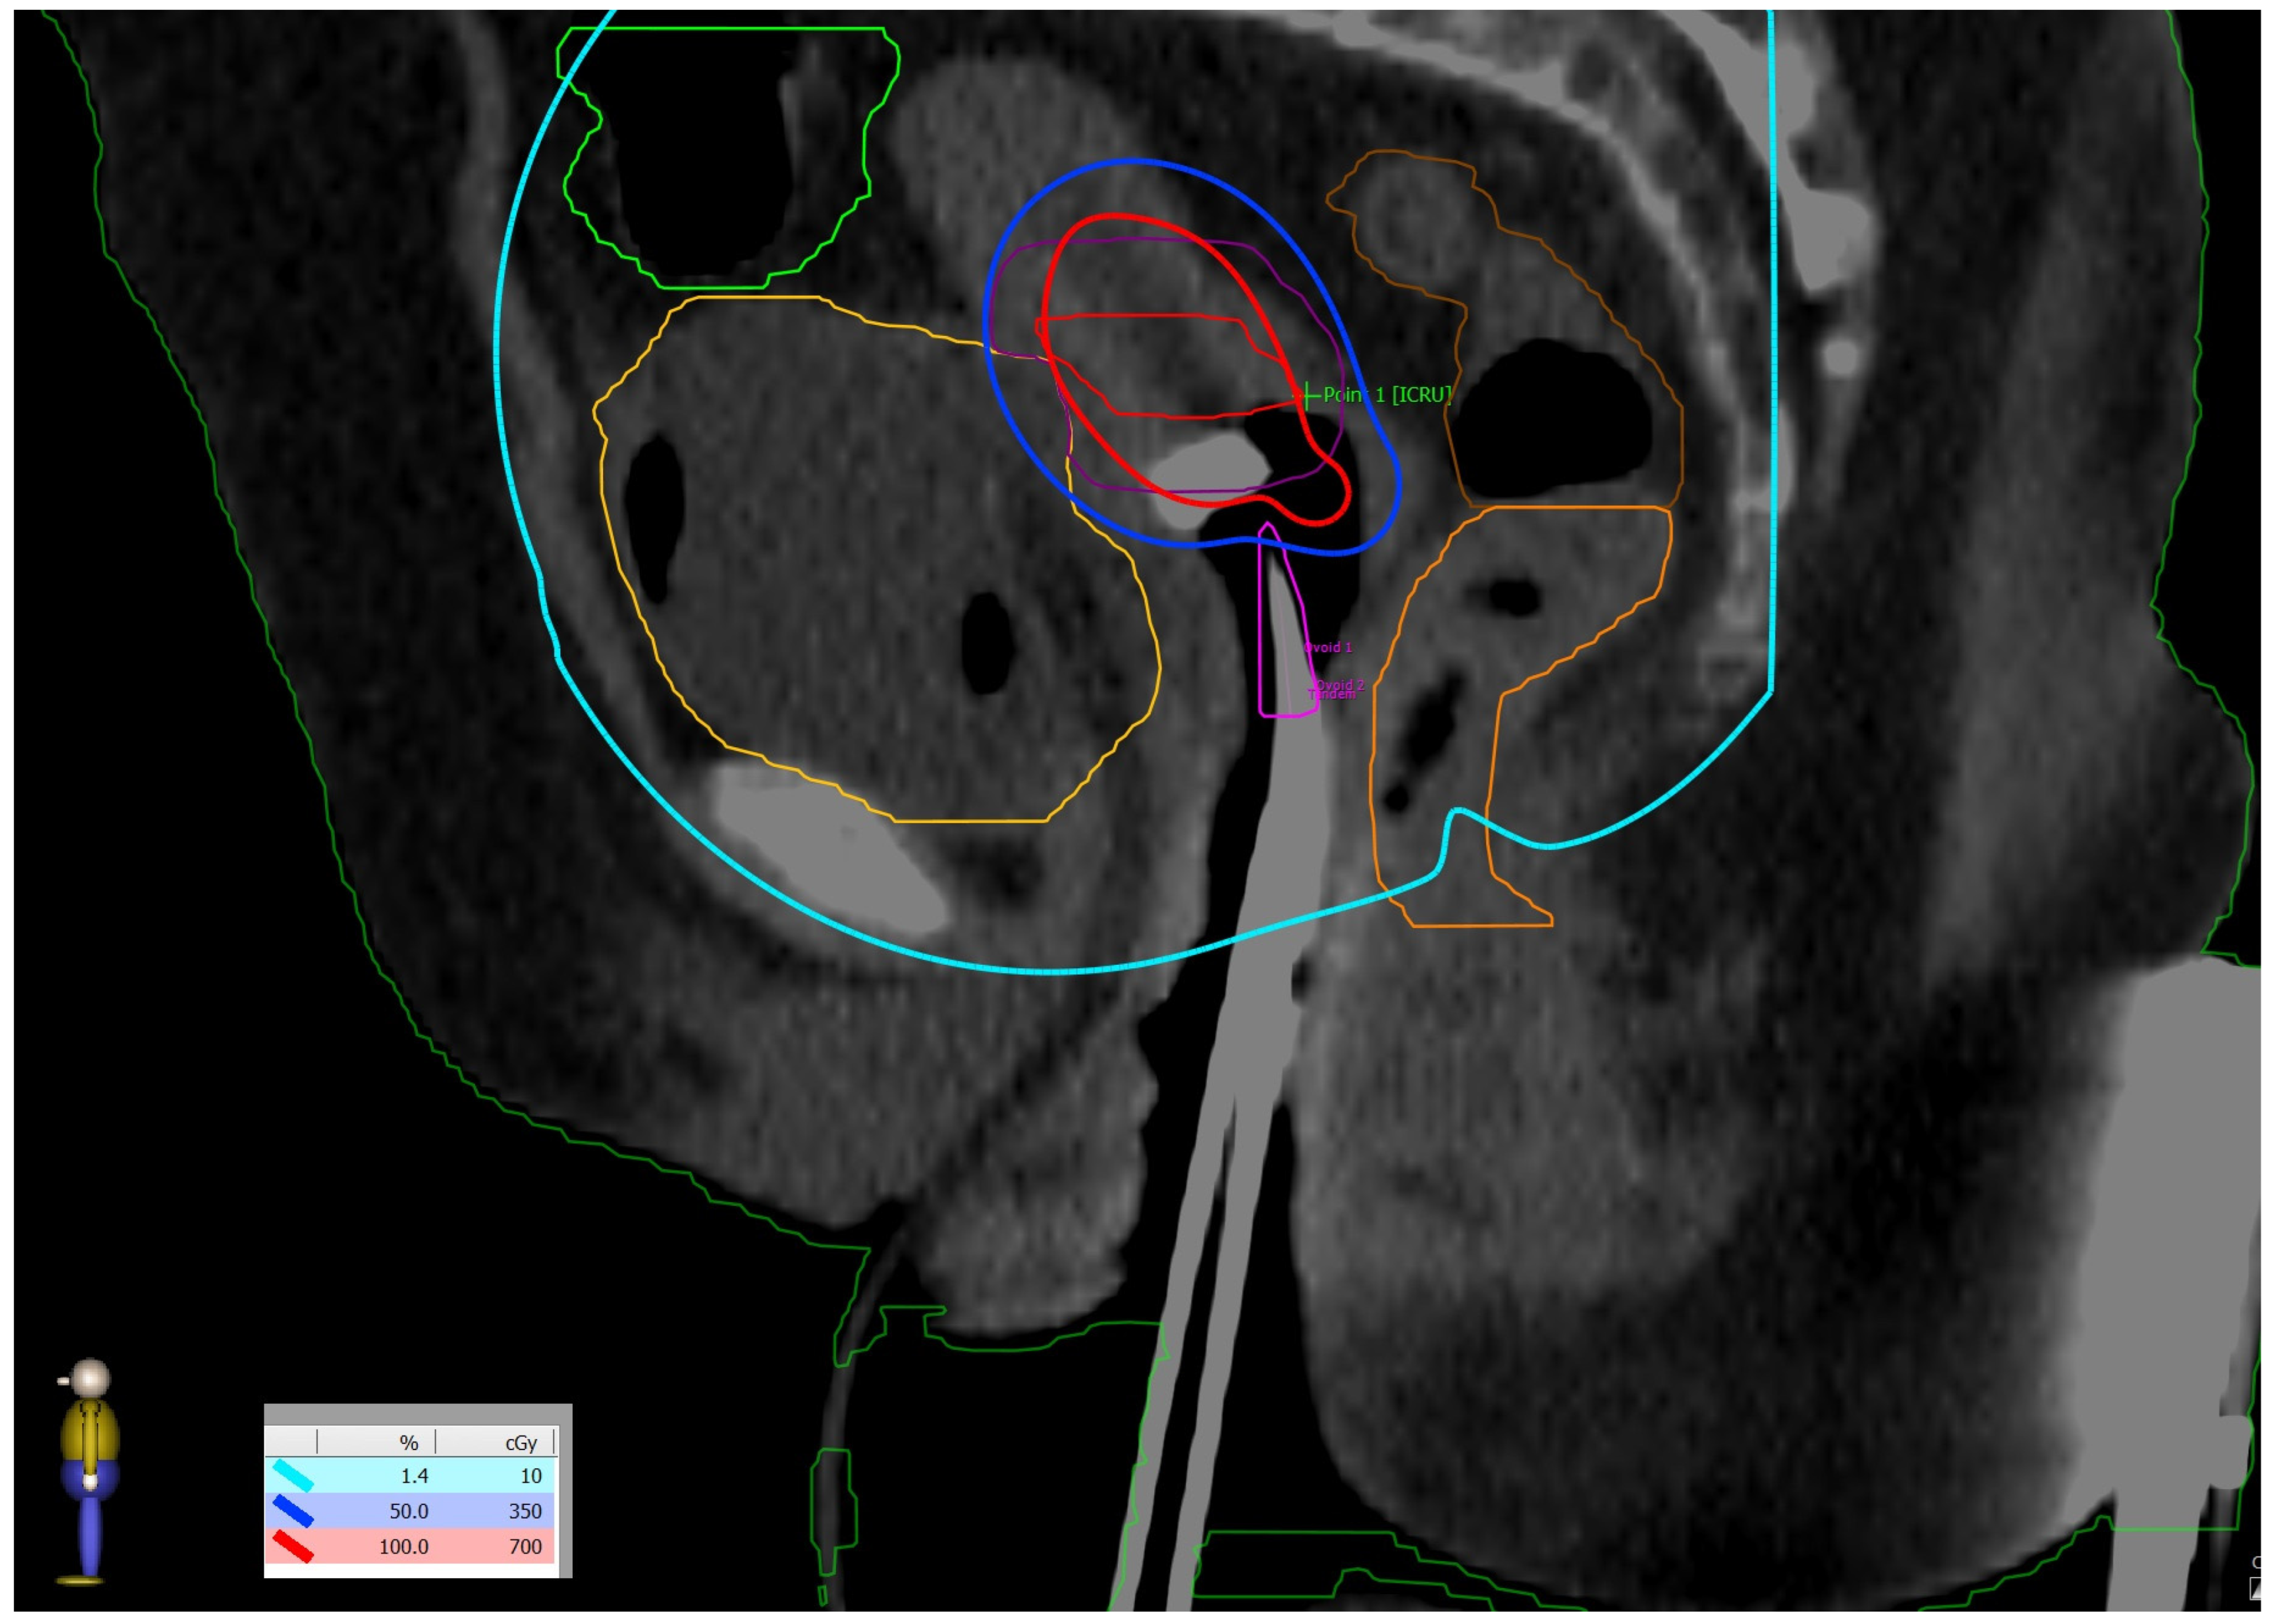

Figure 3.

(Left side): dose distribution from 55 Gy, which is 100% of the prescribed dose (in red) in boosted lymph nodes and 45 Gy (in yellow) prescribed dose in the whole PTV to 10 Gy (in white). (Right side): Three-dimensional reconstruction of the patient’s skin with the distribution of 10 Gy in pink. All regions of existing skin lesions were avoided and received less than 10 Gy.